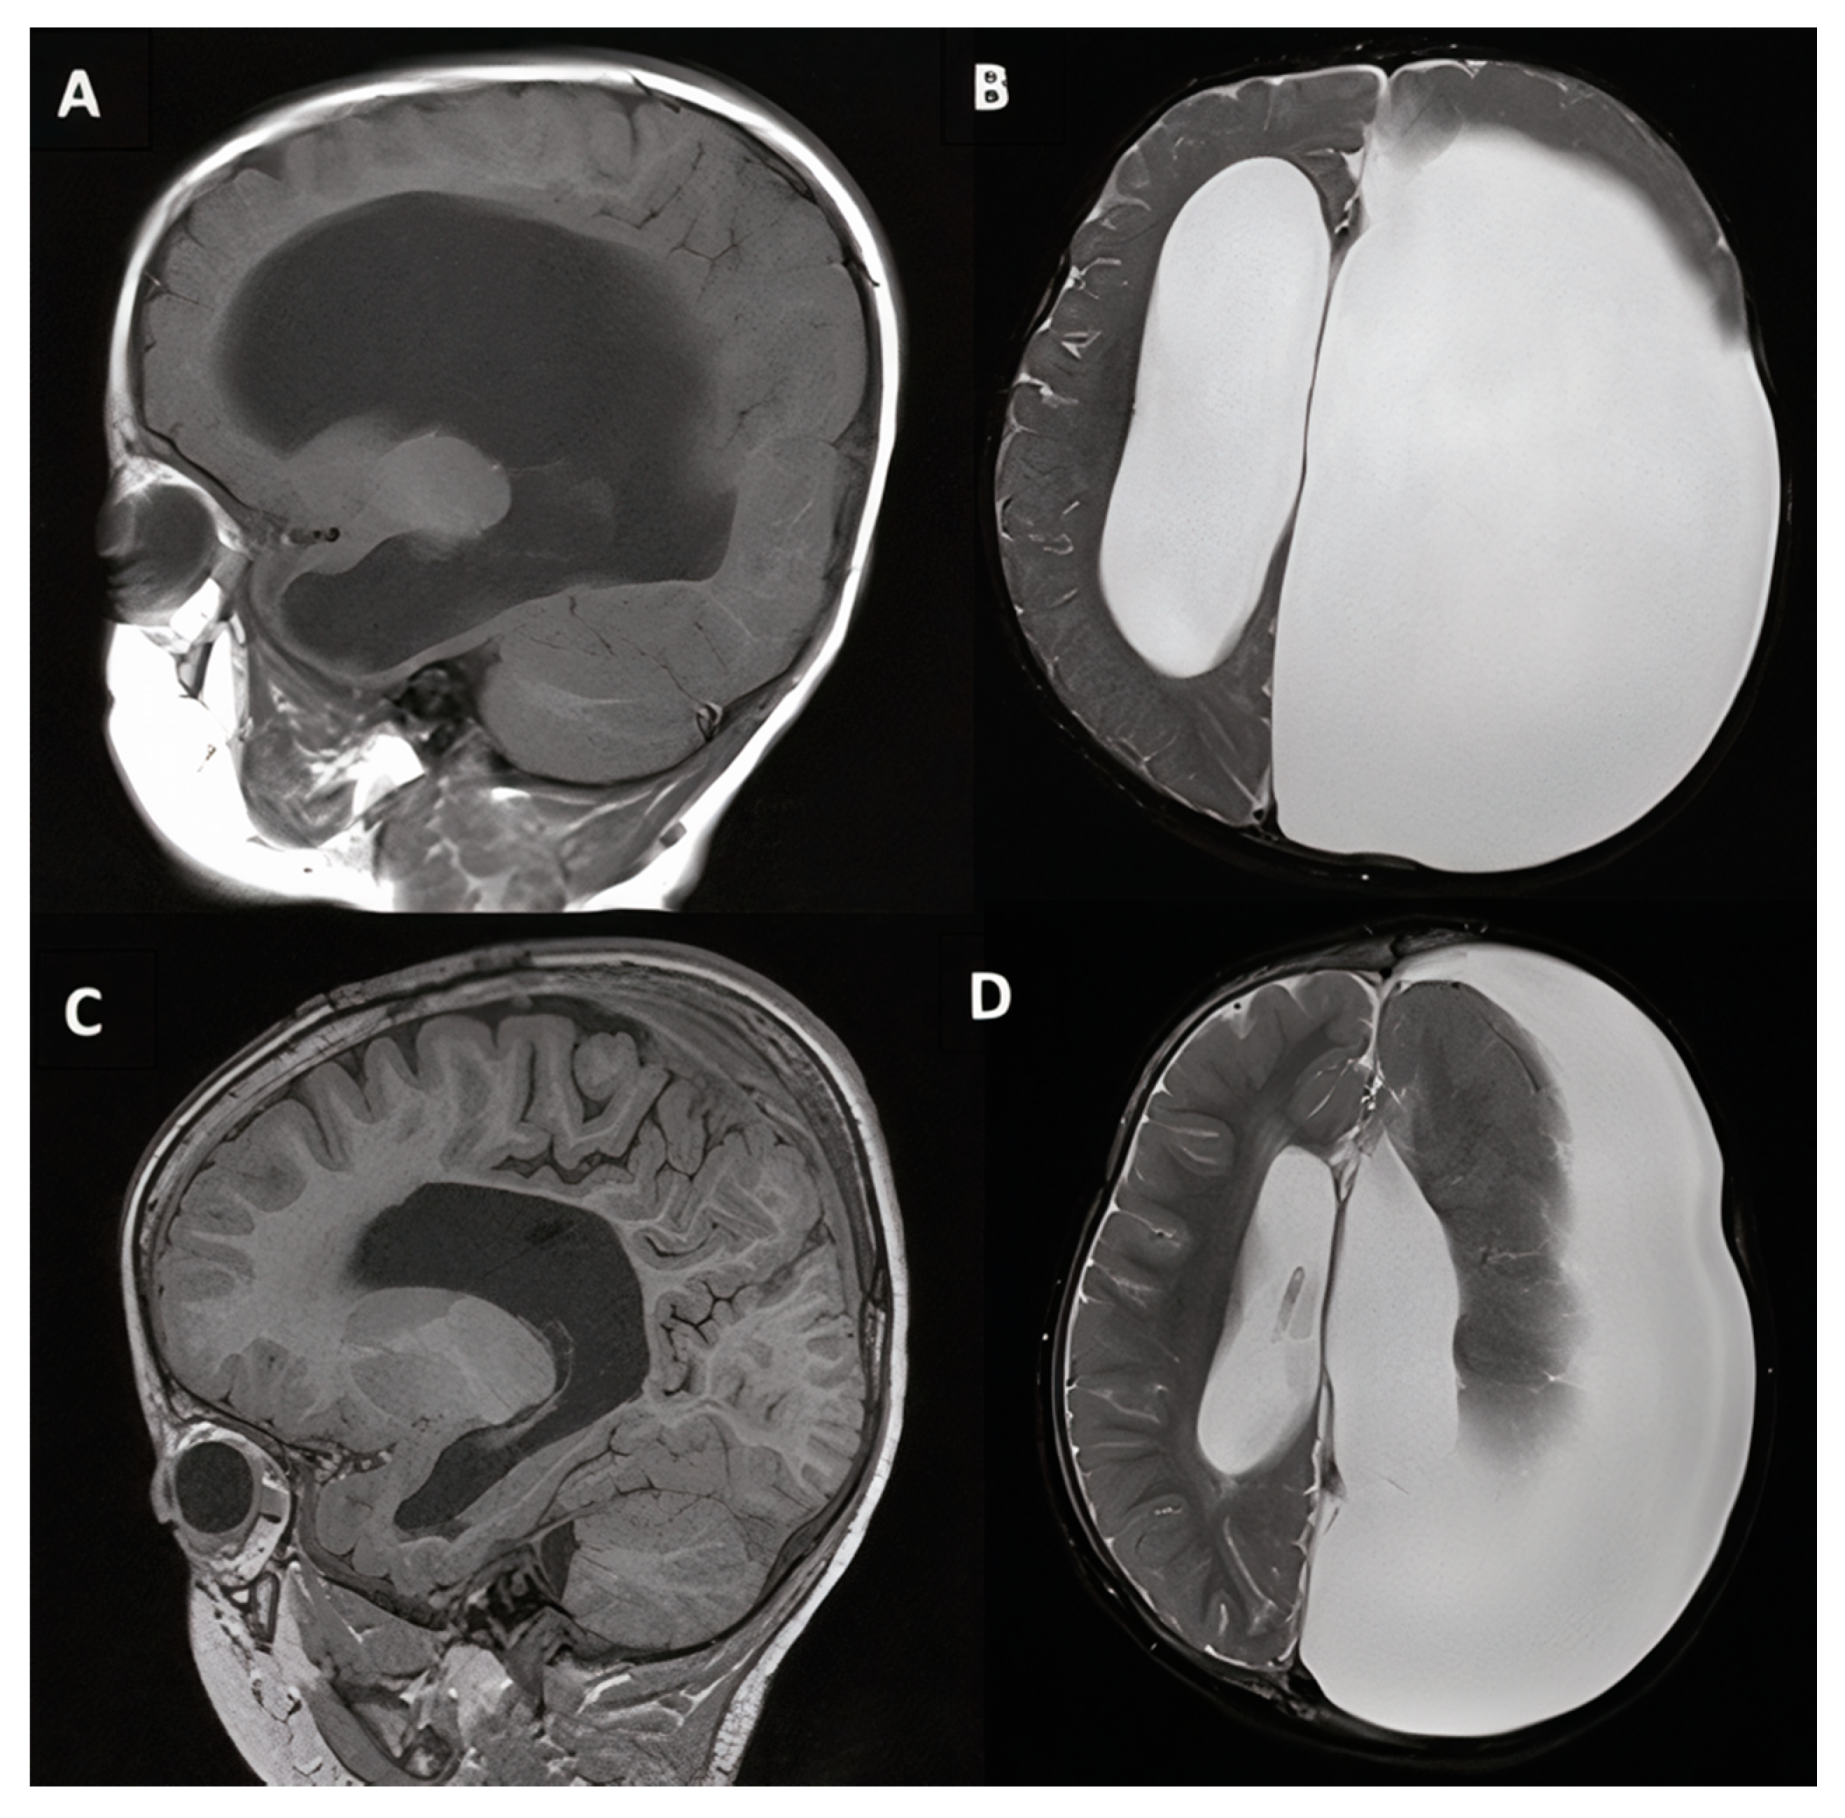

3.1.4. Cases #7–8. Hydrocephalus with Hunter Syndrome

3.1.5. Case #9. Congenital Hydrocephalus Following Intrauterine Stroke

| 7 | 12 y, M |

|

| 8 | 10 y, M |

| 9 | 18 m, M |